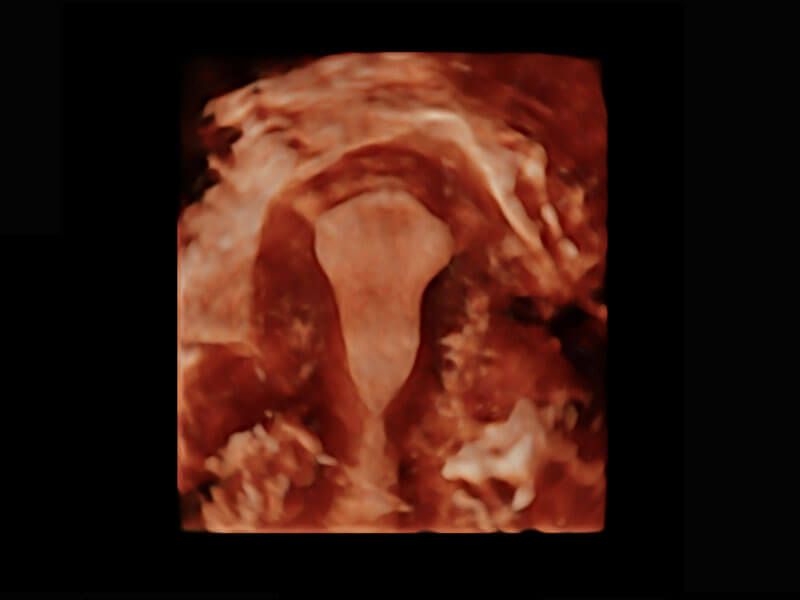

腔内三维-宫内节育器

腔内三维-光影成像

P60为盆底超声检查提供应用方案,多种腔内及腹部容积探头提供从二维、三维到四维的优异图像品质,实时快速三维容积数据获取,专业的测量工具包等人性化设计,为超声医生诊断提供有力保障。